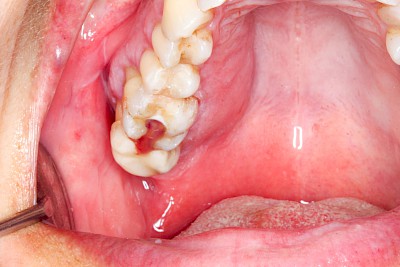

Schwellung ohne Eiter: faltenförmig

Als Sonderform des Reizfibroms können bei Zahnprothesen in den Randbereichen selten am Gaumen, häufiger außen in den Umschlagfalten in Ober- und Unterkiefer auch lappenartige Auffaltungen (Lappenfibrome) beobachtet werden, die ebenfalls aufgrund eines mechanischen Dauerreizes entstehen. Alle diese Veränderungen sind in der Regel eher wenig schmerzhaft – auch wenn man darauf drückt. Hier sollte zeitnah mit einem Zahnarzt eine Abklärung erfolgen.